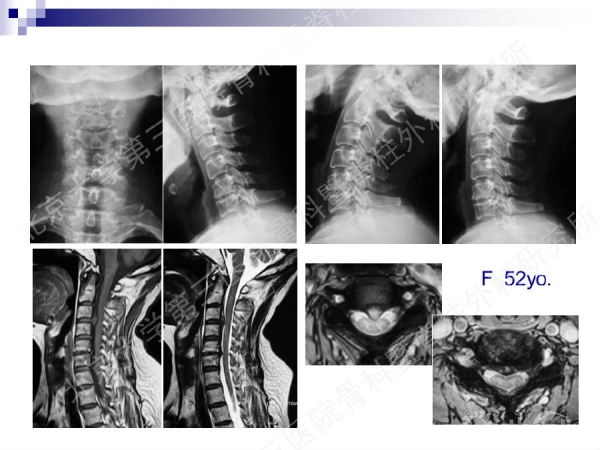

今天,在北京大学第三医院骨科暨脊柱外科研究所刘忠军教授分享的《颈椎人工椎间盘置换手术注意问题》课件中,他将通过大量影像资料、临床研究数据和长期随访结果,给大家介绍现阶段最重要的颈椎非融合技术——人工椎间盘置换术的适应证、禁忌证和其他需要密切注意的一些问题,提醒同道关注与手术技术及内植物相关的尺寸、终板顺列、中心轴线顺列等问题,严格把控手术指征,规范、精准地开展颈椎人工椎间盘置换手术,保障手术疗效。